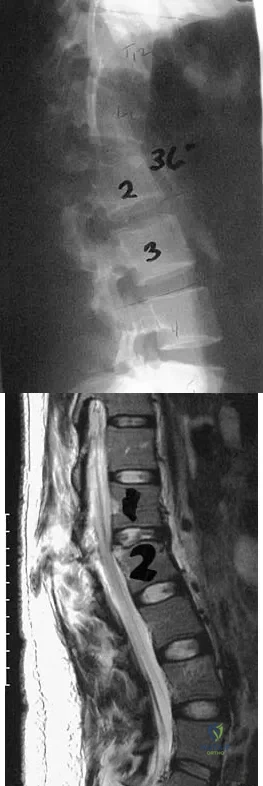

Question 48

Figures 26a and 26b show the radiograph and MRI scan of an 18-year-old man who fell from a trampoline. Examination reveals exquisite local tenderness at the thoracolumbar junction, but he is neurologically intact. Management should consist of